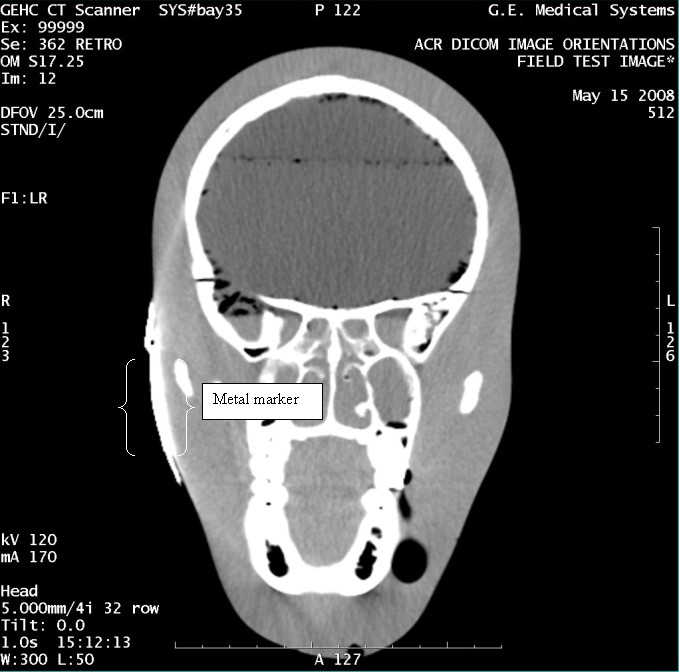

- With the support of the site personnel, examine the images sent

to the Review Station (i.e., 12 series, each with 1 image) and compare

their orientation to the images in this document.

- Each image contains a metal marker on the phantom's right cheek.

- Each image in this document contains a description of the expected

orientation of the metal marker (i.e. to prove Left and Right) as

well as the Posterior and Anterior orientation description.note:

The sample images included in this document use “R”, “L”, “P”, and “A” for “Right”, “Left”, “Posterior” and “Anterior” orientation. The Hospital Review Station may use a different style of annotation. The style used is not relevant to this procedure.

Figure 14. Exam 99999, Series 362